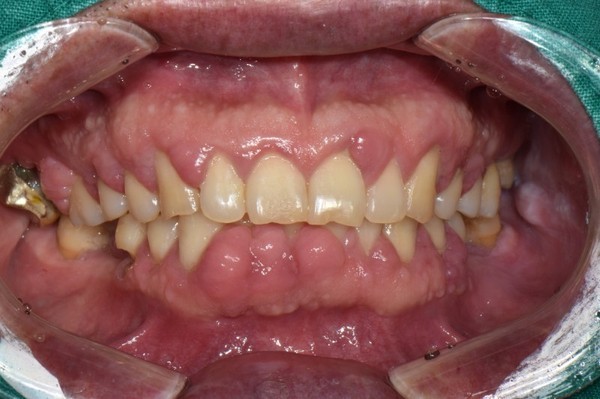

이 병은 미국 치주학회에서 추천했듯이 병의 정도에 따라 다시 몇 가지로 나뉠 수 있는데 치과보험 및 치료계획에 매우 중요하다. 치주병의 임상증상을 통해 환자의 상태에 대한 정확한 정보를 보험 관리자에게 전달할 수 있다. 즉 성인형 지주염을 경도, 중등도, 중증 진행성으로 분류하면 더 정확한 치료계획을 세울 수 있다. 몇몇 환자는 복합된 형태를 보이는데 경도나 중등도인 환자에서 한군데 이상이 심한 부착소실을 보이는 심한 형태의 치주질환이 있을 수 있다.

미국 치주학회는 또한 치은염과 재발성 치주염도 분류했다. 이 분류법으 의사소통과 치료계획 측면에서 유용하나 그 분류가 애매하고 특정 치주감염을 명확하게 규정을 짓지 못한다. 치과의사와 치과위생새를 이한 환자를 성인형 치주염으로 평가하기 위한 다른 분류법이 제안되었다. 부착소실을 바탕으로 한분류법은 성인형 치주염의 파괴정도를 결정하는 데 유용하다.

*1형:치은염-색의 변화, 치은형태, 위치, 외관 그리고 출혈 또는 삼출물이 관칠되는 치은의 염증

2형:초기 치주염-치은염증이 더욱 심화되어 치주조직으로 파급되며 약간의 치조골 흡수가 관찰된다. 약간의 결체조직 부착소실과 치조골 소실이 나타난다.

3형:중등도 치주염-치주염의 심화된 단계 치주파괴가 더욱 진행되고 치조골 지지가 감소되기 시작한다. 치아동요도는 증가되기 시작한다. 분지부 병소가 있을 수 있다.

4형:중증 진행성 치주염-치주염이 더욱 진행되며 치조골 파괴가 심하다. 치아동요도가 심해지며 분지부 병소가 심해진다.

5형:난치성 치주염-적절한 치료후에 부착소실이 계속 진행된다. 다발성 병소를 보인다. 이들 병소는 계속적으로 치주 세균에 감염된다. 적은 부위의 병소를 가지는 환자에게서도 적용되는 항목이다.